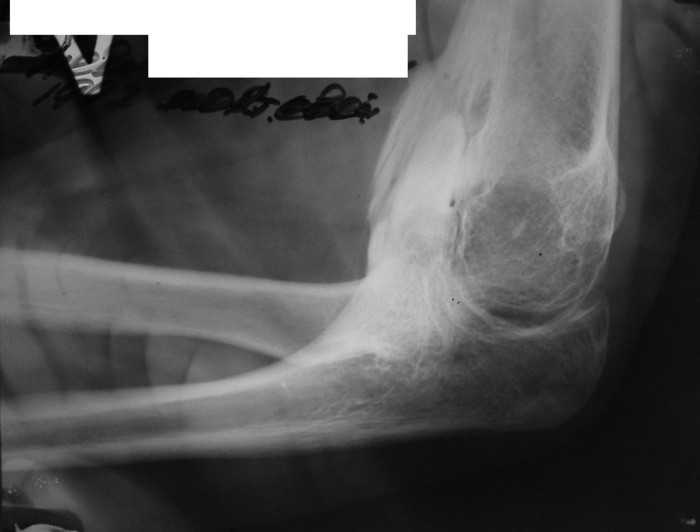

Врожденная аномалия, множественные экзостозы

Анамнез заболевания: со слов матери появлению множественных опухолевидных образований на спине предшествовал массаж воротниковой зоны в 4 года. Консультирован в Областной детской больнице и Областном онкодиспансере. В декабре 2010 г. после падения с велосипеда ушиб левый локтевой сустав, a в январе вторичное падение с велосипеда с ушибом правого локтевого сустава, после чего пациент отметил постепенное ухудшение функции обеих верхних конечностей вплоть до резкого ограничения объема движений в обеих плечевых и локтевых суставах.

Место болезни: при осмотре определяется - вынужденное положение верхних конечностей в плечевых и локтевых суставах, множественные опухолеподобные образования вдоль позвоночника и по наружной поверхности верхней трети левой бедренной кости округлой формы, с четкими контурами, неподвижные, безболезненные, каменистой плотности. приводяще-отводящая контрактура в обеих плечевых суставах, сгибательно-разгибательная контрактура в обеих локтевых суставах с сохранение про- и супинационных движений. Объем движений в пальцах кисти и лучезапястных суставах в полном объеме без ограничений, безболезненный.

Диагноз: врожденная аномалия развития шейного отдела позвоночника с резким нарушением функции в плечевых и локтевых суставах, множественных костно-хрящевые экзостозы, оссифицирующий миозит.

рентгенограммы

это fibrodysplasia ossificans progressiva, генетически обусловленная прогрессирующая метаплазия соединительной и мышечной ткани в костную. Лечится (вернее, тормозится) консервативно, после попыток оперативного лечения и после травм - прогрессирует.